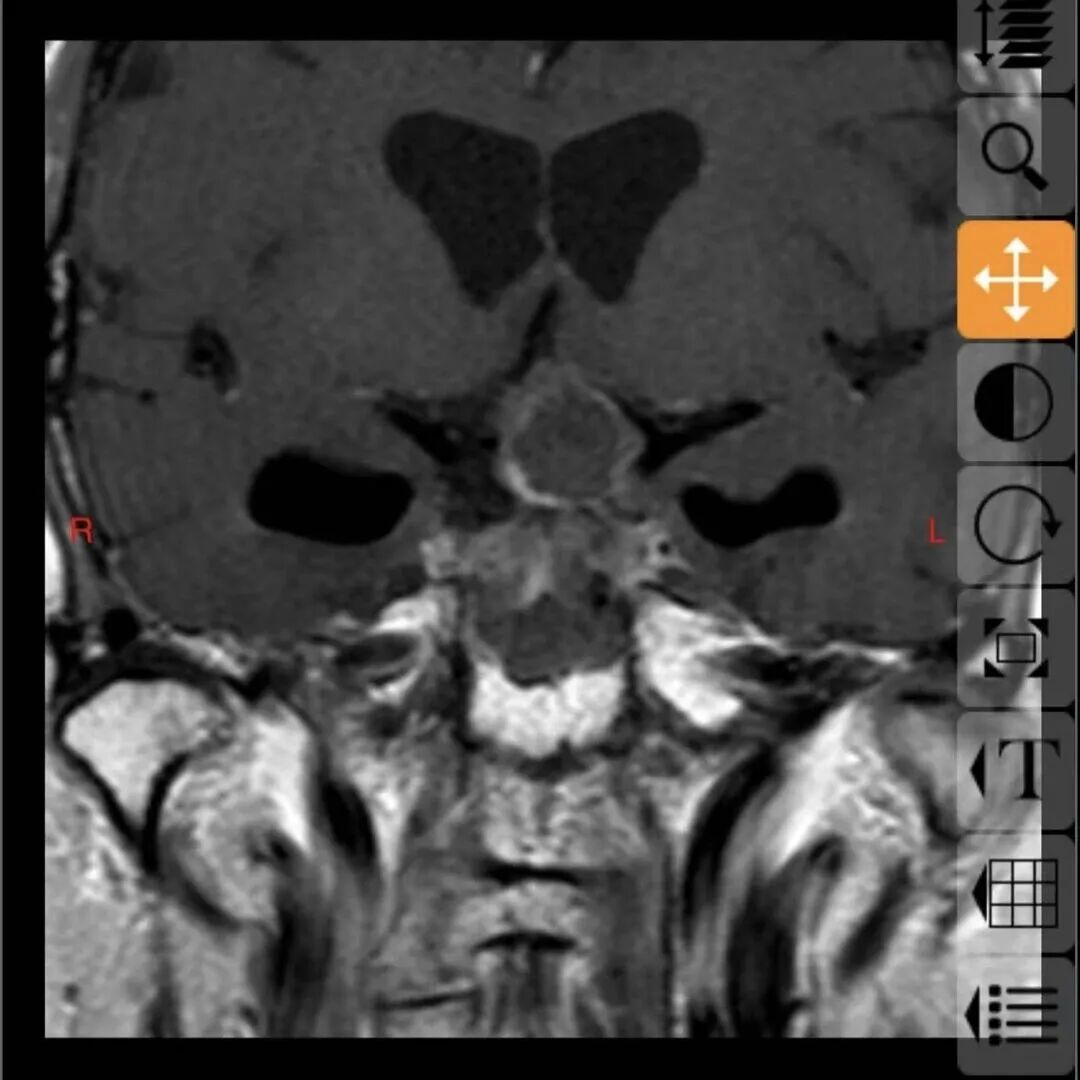

68岁的邓大叔是一位饱受垂体瘤困扰的“老战士”,11年前他经鼻行垂体瘤手术,几年后垂体瘤复发再次通过伽马刀治疗,经过两次历练后的他以为之后就可以高枕无忧,没想到近期的复查报告显示肿瘤“卷土重来”,且这次情况远比之前“棘手”,复发的肿瘤不仅从鞍内生长到鞍上,还与大脑的“生命线”——前交通动脉以及掌管意识记忆的三脑室底粘连紧密,甚至朝一侧颈内动脉上方生长,就像一颗埋在大脑深处的“不定时炸弹”,位置险要,结构复杂。

这颗复杂的“炸弹”究竟该如何拆除?张治国主任仔细研究了邓大叔的病情后,提出了一个大胆的方案:再次施行经鼻蝶微创手术。

最终,由张治国主任主刀,为邓大叔顺利实施了这例高难度的经鼻蝶微创手术,肿瘤被完整、精准地切除,紧密粘连的前交通动脉及三脑室底均保护完好。